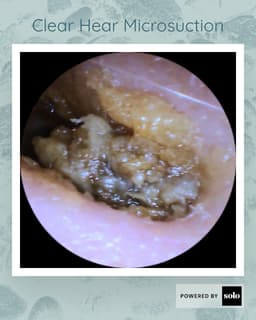

A small camera will assess your membrane health and ear canal. This is a quick painless procedure pictures can be forwarded to your Gp if necessary. Please note we understand if you need to cancel, but a no show you will be charged £25 .Please let us know within 24hrs of your allocated time . PLEASE NOTE THIS IS FREE AND IGNORE IF THE SYSTEM ASKS YOU TO PAY A DEPOSIT!!!I We are trying g to fix this error .